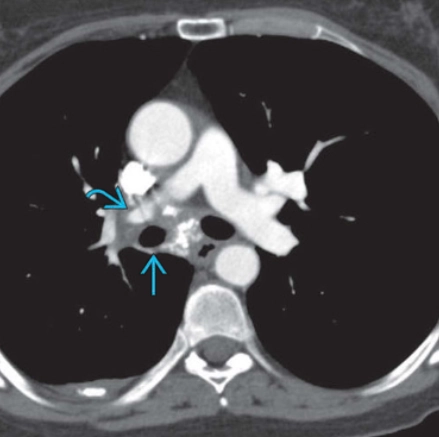

Viêm trung thất xơ hóa (Fibrosing mediastinitis)